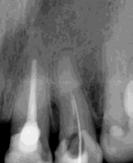

Las Figuras 1-3 muestran las imágenes de la cavidad bucal de la paciente. Se puede observar el deterioro generalizado de la salud bucodental, destacando la higiene dental deficiente, gingivitis, restauraciones dentales desajustadas, exposiciones radiculares, anodoncias parciales y caries radiogénica.

Las Figuras 4-13 son imágenes radiográficas de los dientes de la paciente que presen tan múltiples lesiones periapicales como consecuencia de las necrosis pulpares originadas por la radioterapia. Se realizaron los

tratamientos y retratamientos endodónticos necesarios para preservar los dientes en boca, evitando las exodoncias y por lo tanto minimizando el riesgo de generar osteorradionecrosis.